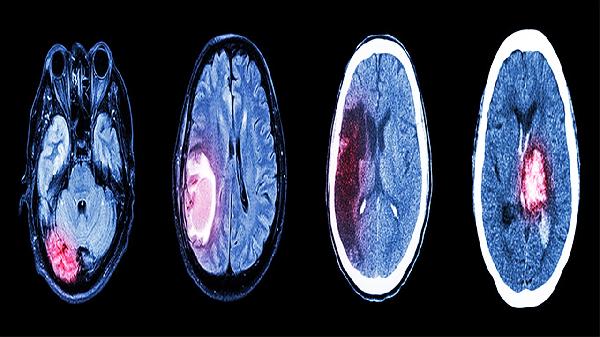

建议保持规律作息和适度运动,每日进行颈部放松操,避免长时间低头。饮食注意补充镁元素如坚果、深绿色蔬菜,限制咖啡因摄入。若疼痛每周发作超过2次或伴随呕吐、视物模糊等症状,需及时进行头颅CT或MRI检查排除器质性疾病。情绪管理可尝试正念冥想或心理咨询,必要时在医生指导下短期使用抗焦虑药物。